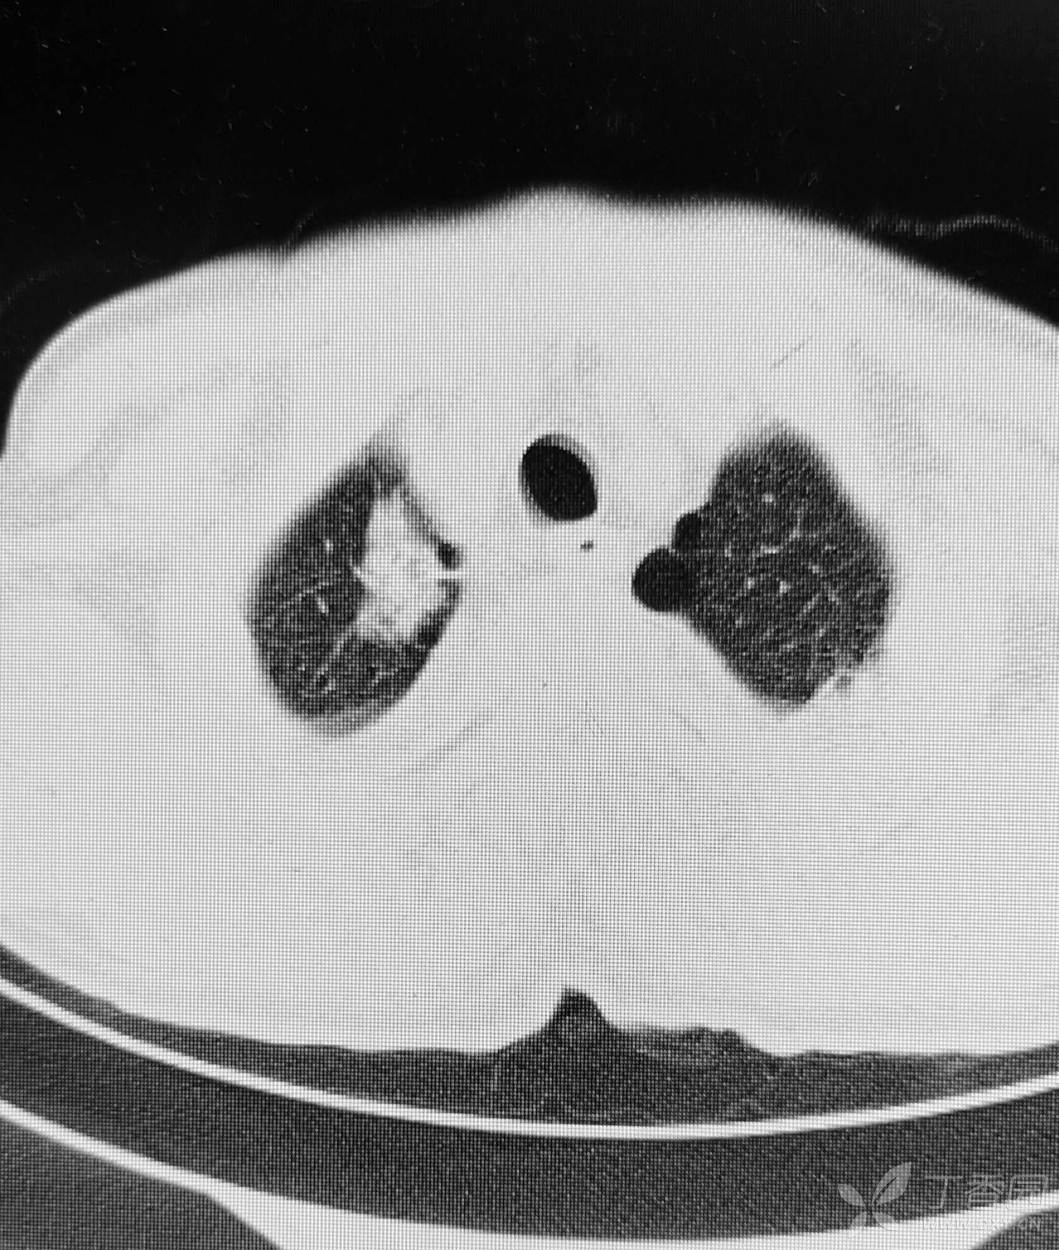

直肠癌术后两个月,接受放化疗一个月。白细胞危急值。

停化疗放疗,升白药物。白细胞增高了。

血小板仍低,血红蛋白开始降低。

胸部影像如图。

目前有血培养阳性,病原菌难以命中。痰培养阳性。